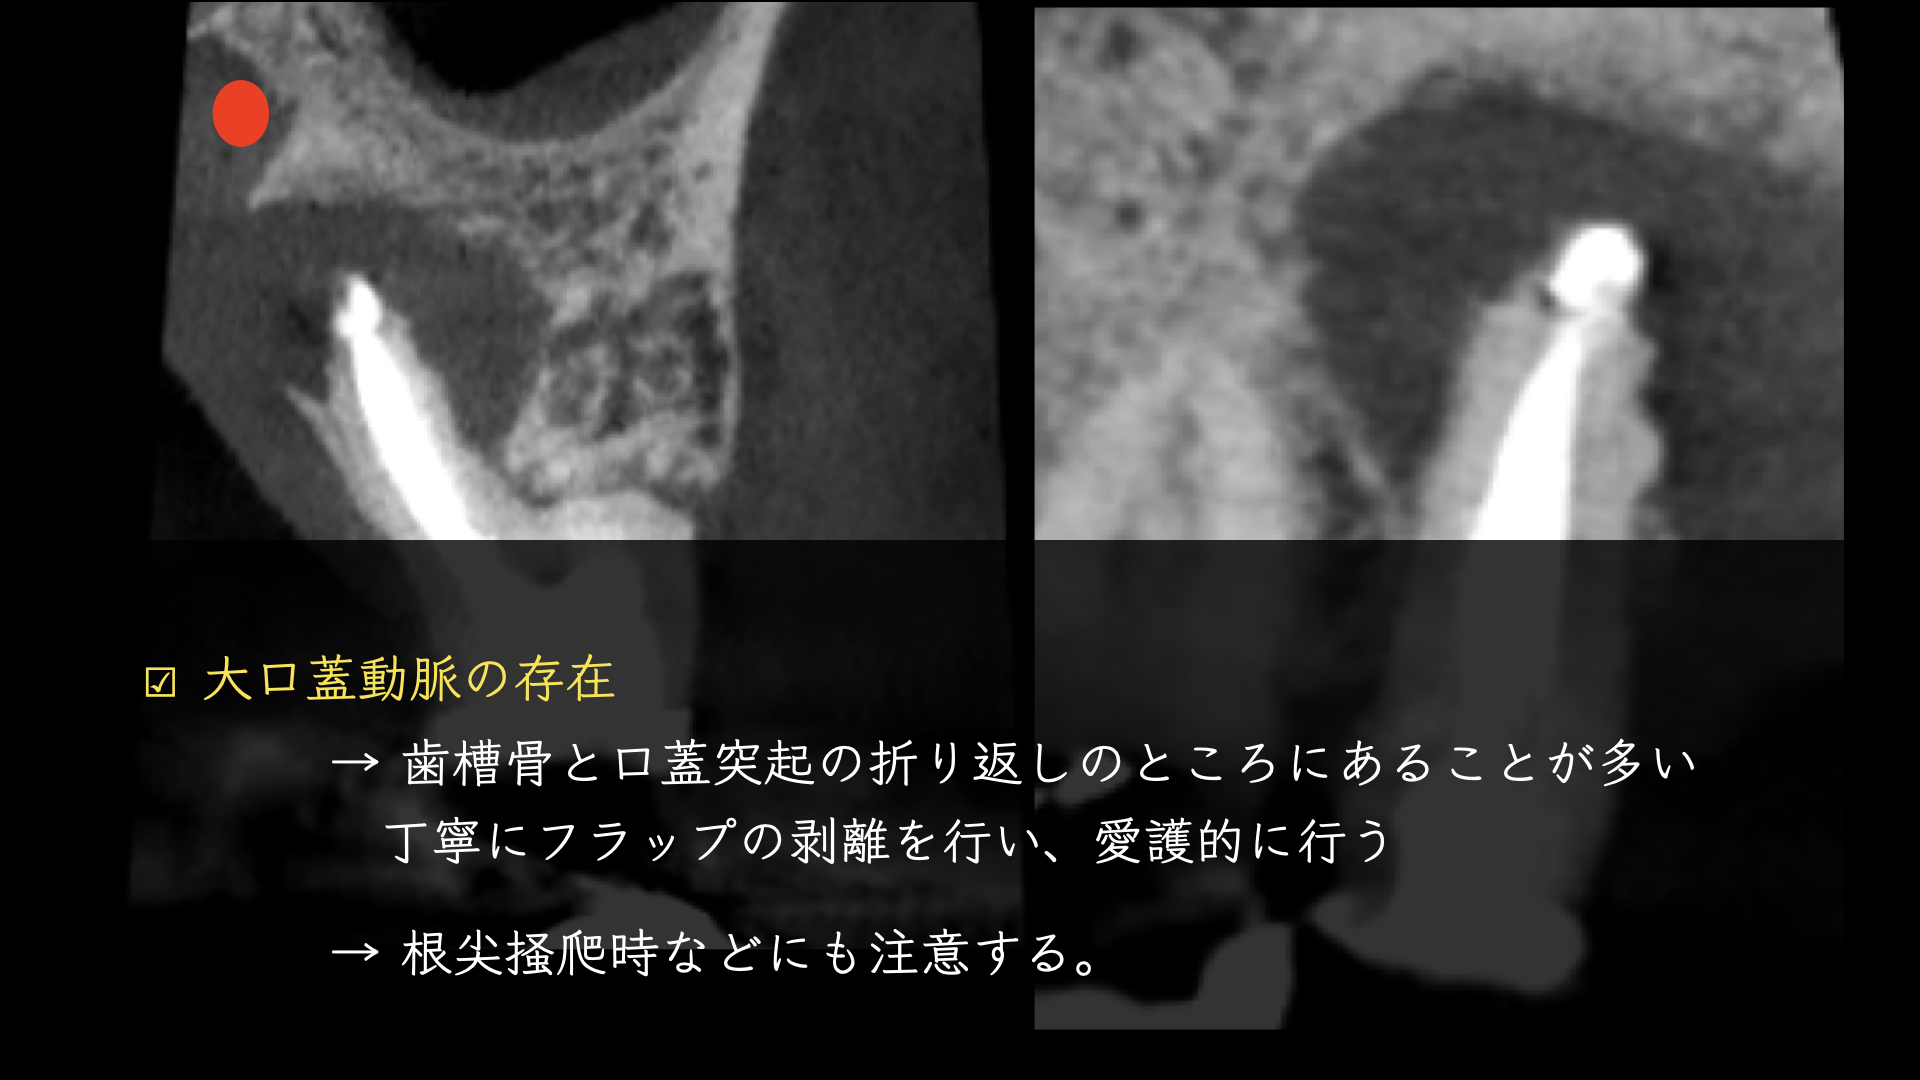

適応症ではないのは大口蓋動脈の存在です。

論文より今回のケースは安全であると判断し、歯根端切除で対応しました。

注意しておこないました。